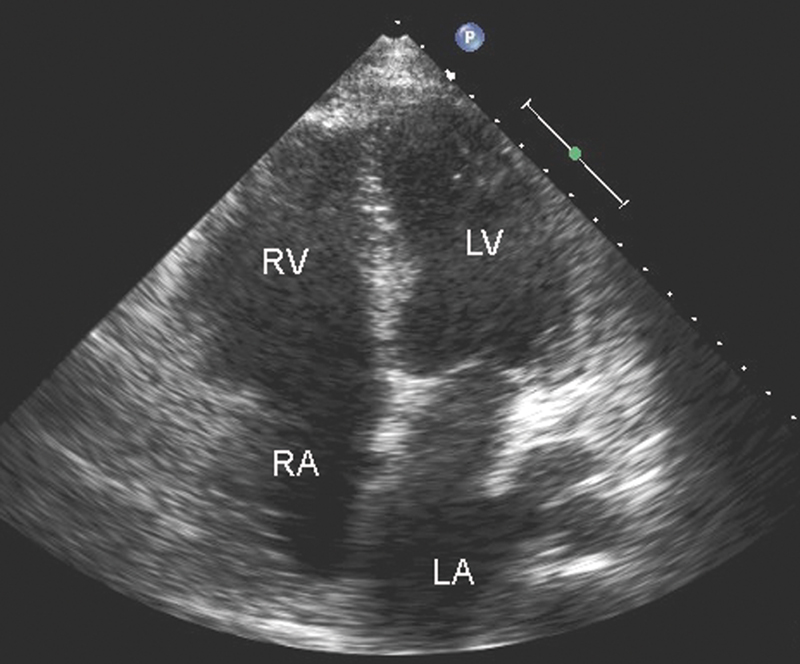

فحوصات تشخيصية لبعض امراض القلب والشرايين التاجية